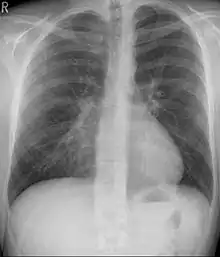

التصوير الشعاعي للصدر يساعد في تشخيص المرض بشكل كبير. كما ان التصوير الشعاعي في الصدر المقعر يُظهر بعض الغموض في بعض الأحيان في الرئة اليمنى لأنها أكثر تعرضاً لاستنشاق للأجسام الغريبة (مثلما يحدث في الاتهاب الرؤوي).[15] كما تشير بعض الدراسات على استخدام مؤشر هالر ويحسب بناءا على التصوير الشعاعي بدلاً من الفحص بالأشعة المقطعية للأشخاص الذين لديهم تعارضات مع الأشعة المقطعية.[16]